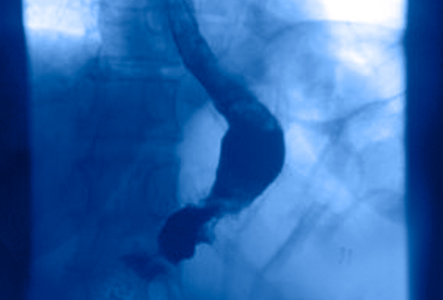

También conocida como gastrectomía vectorial o simplemente la «manga», esta cirugía bariátrica consiste en remover del 70% al 80% del estómago y modificar su forma a un largo estómago tubular.

La gastrectomía en manga por vía laparoscópica es de los procedimientos de la cirugía bariátrica más realizados a nivel mundial debido a sus satisfactorios resultados y el margen de éxito.

En la cirugía de manga gástrica, el cirujano extrae parte del estómago y construye un tubo estrecho. El nuevo estómago en forma de plátano es mucho más pequeño que el estomago original, por lo que la persona comerá menos cantidad de alimentos, se saciará rápidamente y tendrá menos hambre a lo largo del día.